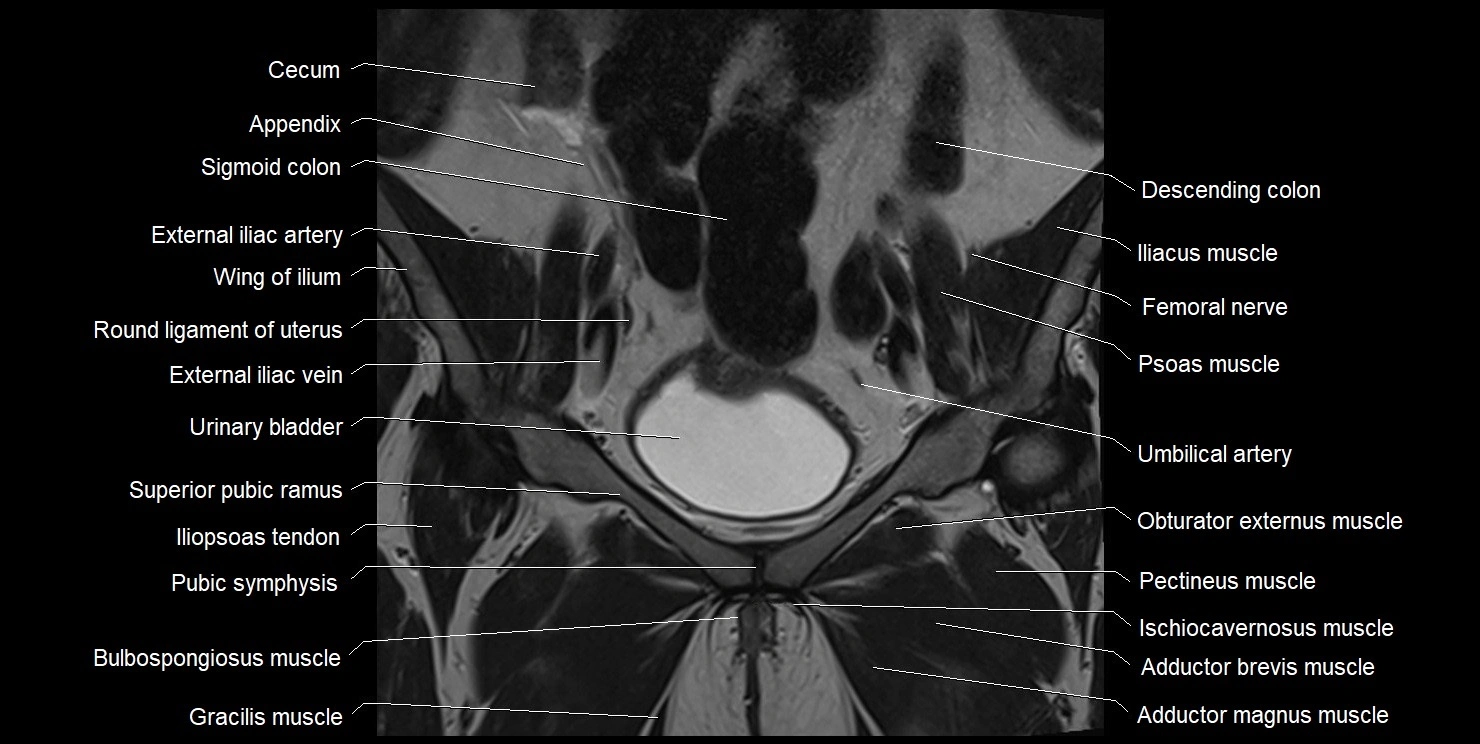

- Acetabulum

- Adductor brevis muscle

- Adductor magnus muscle

- Ala of ilium (wing of ilium)

- Cecum

- External iliac artery

- External iliac vein

- Gracilis muscle

- Iliopsoas muscle

- Iliopsoas tendon

- Pectineus muscle

- Pubic symphysis

- Obturator externus muscle

- Obturator internus muscle

- Umbilical artery

- Urinary bladder